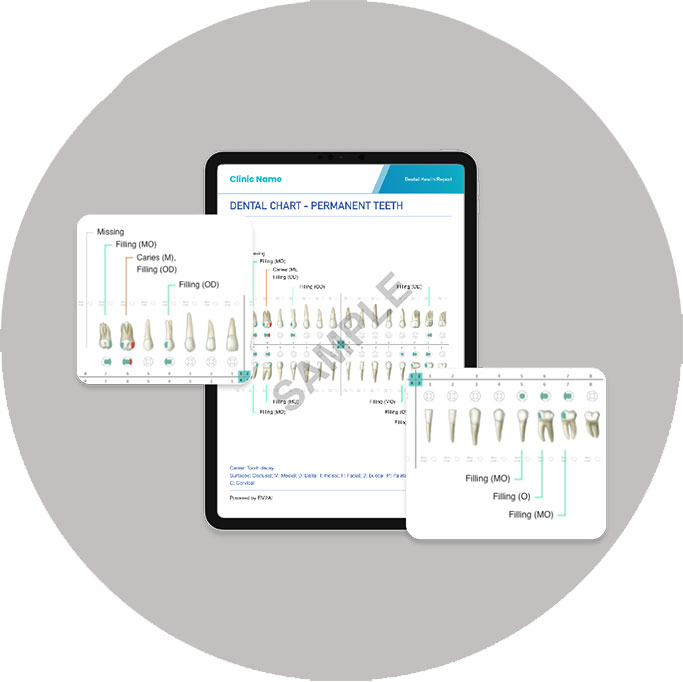

AI Dental Health Report

After your visit, you will receive an easy-to-understand personalised dental health report via Q & M mobile App. This report summarises the clinical findings, verified by your dentist, and includes annotated images for your reference.

Benefits:

- Your personal, portable dental records

- Convenient access anytime, anywhere

- Great for follow-ups, especially if you no longer reside in Malaysia

AI Dental Health Report

After your visit, you will receive an easy-to-understand personalised dental health report via Q & M mobile App. This report summarises the clinical findings, verified by your dentist, and includes annotated images for your reference.

Benefits:

- Your personal, portable dental records

- Convenient access anytime, anywhere

- Great for follow-ups, especially if you no longer reside in Malaysia